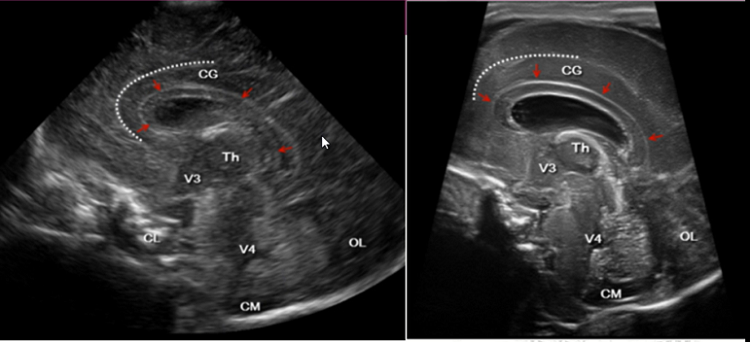

颅脑超声切面示意图

颅脑超声不仅适用于新生儿,还适用于前囟未闭的婴幼儿颅内病变的筛查及诊断,利用超声仪器通过小儿尚未闭合的囟门(前囟、侧囟、乳突囟、后囟,主要为前囟)对颅内结构及病变进行检查及诊断,可提示颅内病变的类型、程度、部位,可作为高危新生儿的常规筛查手段。

三、颅脑超声检查及复查时间

1.颅内出血

绝大多数发生在生后3天内,生后1周内的检出率为90-95%,严重且不稳定的颅内出血应酌情及时复查,一般为1-2个月后观察出血吸收情况。

2.缺氧缺血性脑病

出生3天内观察有无脑水肿,1周后复查有无完全恢复,1月后复查是否存在遗留病变。

3.脑室周围白质软化

出生后3天内观察有无脑白质损伤,1周后复查有无恢复,3-4周后观察有无白质软化,3-4个月后复查了解软化灶有无消失及有无脑室扩张。